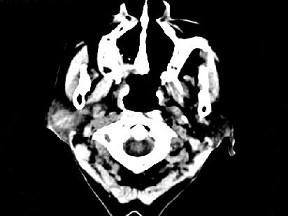

问题 女,72岁,六年前于右面颊部扪及一包块,缓慢增大,其表面较光滑,CT如图所示,该病例应诊断为 ( )

选项 A、颈部淋巴瘤 B、小唾液腺瘤 C、腮腺混合瘤 D、颈部神经纤维瘤 E、Worthin瘤

答案 C